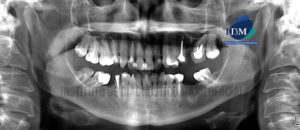

186 – Conducto radicular lateral en pieza 1.2